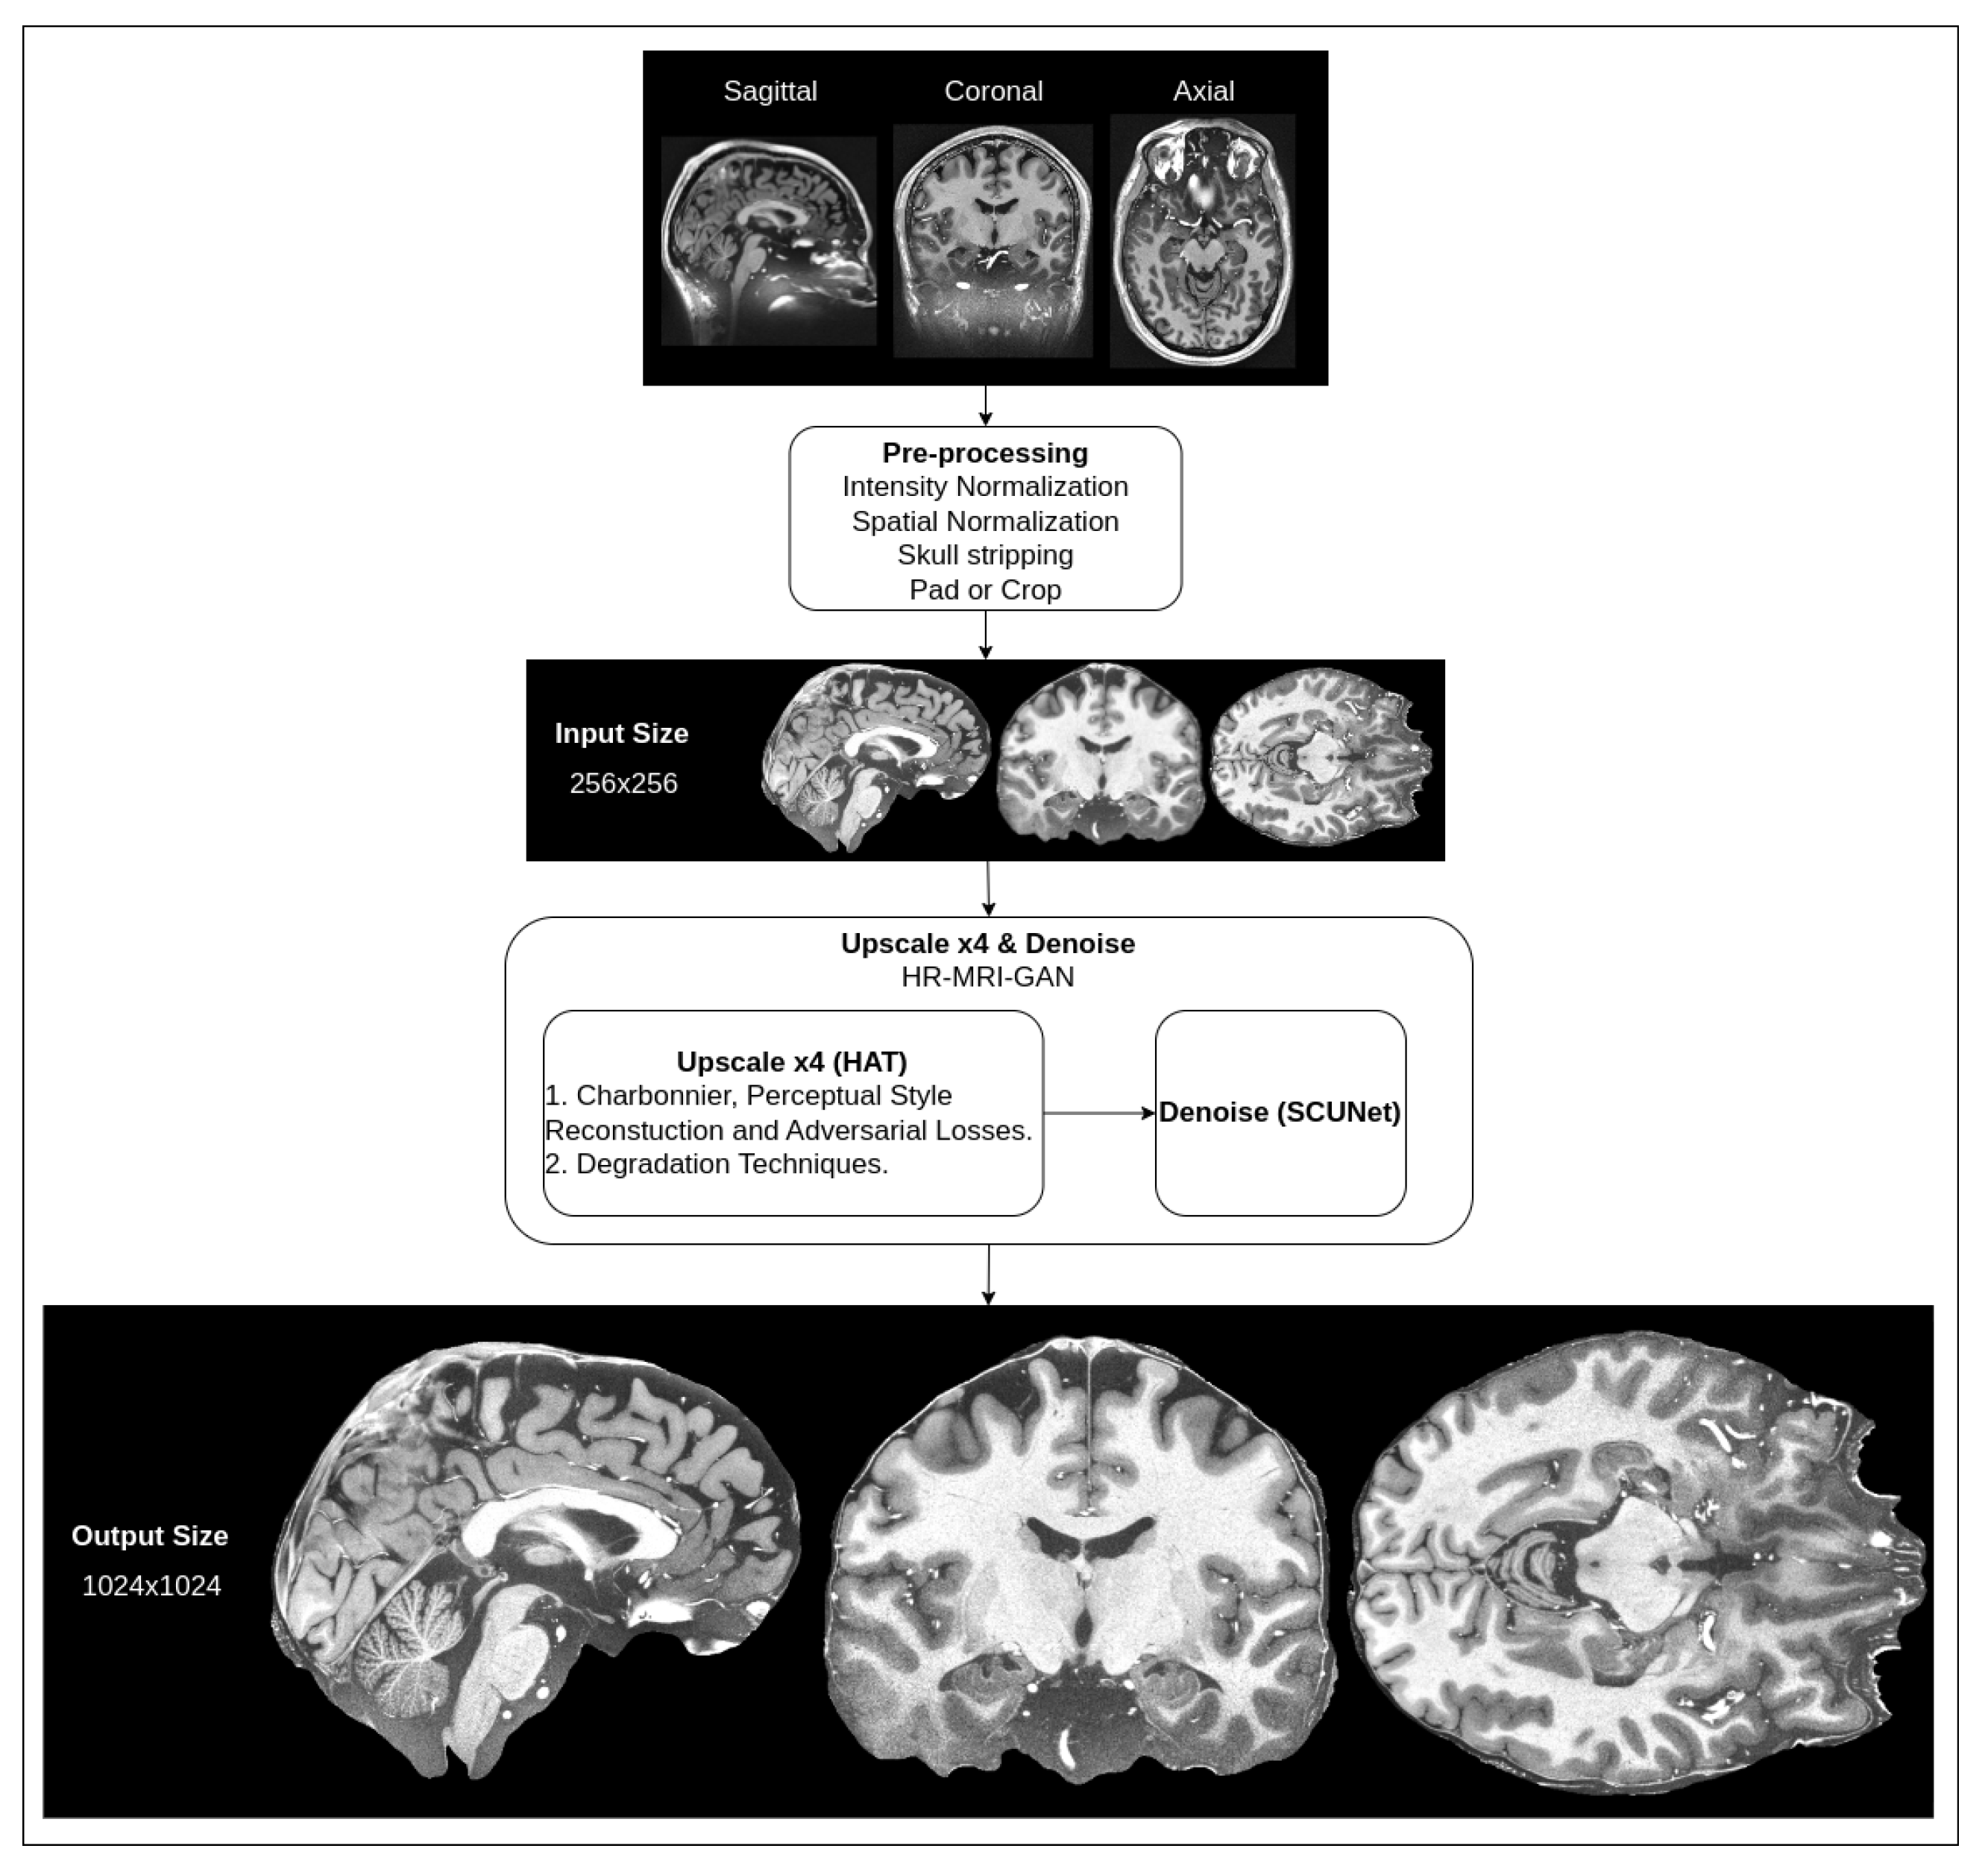

3. Materials and Methods

3.1. Upscale Network

3.1.1. Degradation

3.1.2. Loss Functions

3.2. Denoise Network